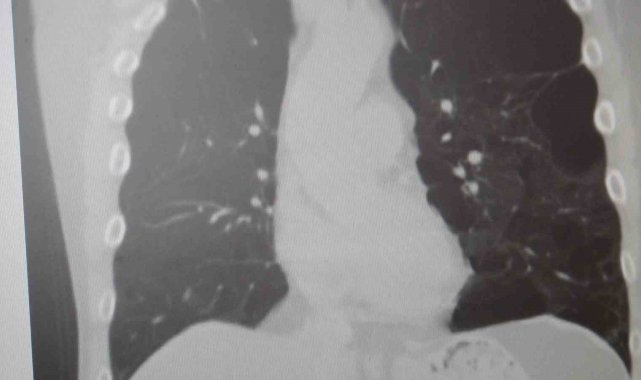

"KOAH toplumda sık görülen bir hastalıktır ve yaklaşık toplumda bunu yüzde 10 civarında görüyoruz. KOAH, zararlı maddelerin akciğeri parçalamasıyla oluşan bir rahatsızlık ve bunun da en önemli nedeni sigara. Vakaların aşağı yukarı yüzde 85'i sigara kullanımından kaynaklıdır. Bunun dışında hava kirliliği, iş yerlerinde kimyasal maddelere maruz kalma ve enfeksiyonlar da yine KOAH'ın nedenleri arasındadır. KOAH'ın önemi şu; bugün Dünya Sağlık Örgütü'nün (DSÖ) dünyada insanları öldüren hastalıklar listesinde ilk 10'da 4'üncü sırada yer alıyor. KOAH önlenebilir bir rahatsızlıktır; sigaranın bırakılmasıyla birlikte tamamen ortadan kalkacaktır."

KOAH'ın akciğer dokusunu tahrip eden bir hastalık olduğunu ve bu nedenle de hastaların enfeksiyona açık hale geldiğine dikkat çeken Karakurt, "Akciğer dokusunun tahrip olduğu her durumda hastaların enfeksiyona karşı eğilimi artar ve enfeksiyona yakalandıkları zaman bunun geçmesi güç olur. KOAH'lı hastalar zatürre geçirdikleri zaman öksürük ve balgam artışı gibi bir takım belirtiler gelişir. Ayrıca ateşin 38,5 derecenin üstüne çıkması, nefes darlığının artması, titremeyle birlikte ateşin yükselmesi ve bir takım bilinç bozukluğu gibi belirtiler hastanın zatürre olduğunu gösterebilir. Bu nedenle hastaların erkenden doktora başvurmaları önemlidir" şeklinde konuştu.